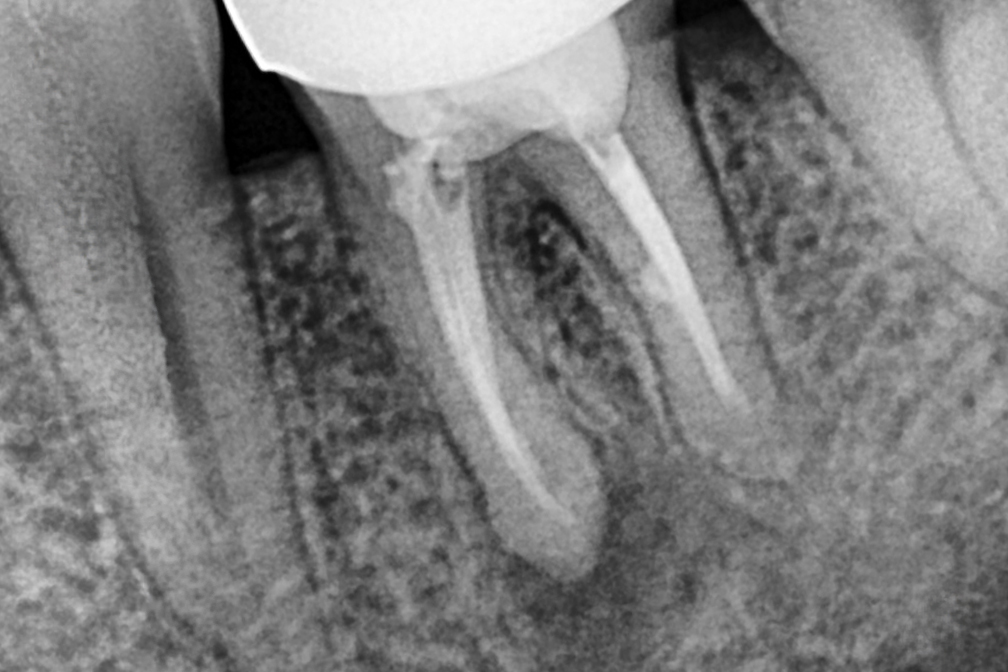

After 2025년 12월 23일